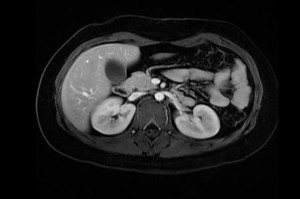

Resonancia magnética de abdomen es un examen de imagen que utiliza imanes y ondas de radio potentes para crear imágenes del interior del área abdominal. No emplea radiación (rayos X). Las imágenes por resonancia magnética solas se denominan cortes y se pueden almacenar en una computadora o imprimir en una película. Un examen produce docenas o algunas veces cientos de imágenes.

Algunos exámenes requieren un tinte especial (medio de contraste). La mayoría de las veces, el tinte se administra a través de una vena (IV) en la mano o el antebrazo antes del examen. Este medio de contraste ayuda al radiólogo a observar ciertas áreas más claramente.

Una resonancia magnética del abdomen proporciona imágenes detalladas del área ventral desde muchos planos. Con frecuencia, se utiliza para clarificar hallazgos de radiografías o tomografías computarizadas previas.

Una resonancia magnética puede diferenciar tumores de tejidos normales. Esto puede ayudarle al médico a conocer más acerca del tumor, como el tamaño, la gravedad y la propagación, lo cual se denomina estadificación.